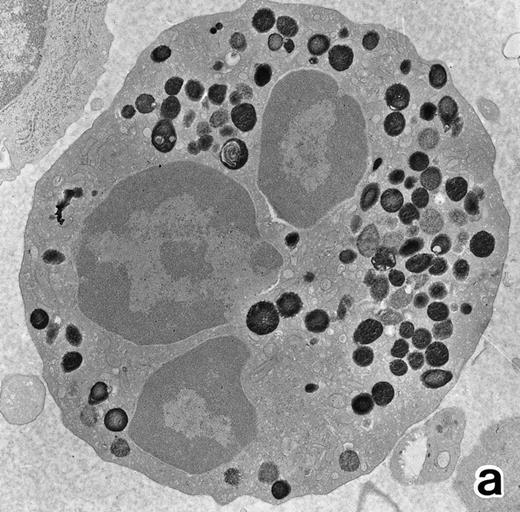

(a) A PMN in patient no. 1 that appeared in the bone marrow after 3 weeks of ATRA treatment. There are numerous granules in the cytoplasm, including spherical, elongated, and even dumbell-shaped granules, all of which are MPO-positive, ie, primary granules. A lipid droplet (L) is also present. (MPO-stained section, original magnification × 15,200.) (b) Higher magnification of a portion of the cytoplasm in (a). MPO-negative secondary granules are not seen. (MPO-stained section, original magnification × 30,900.)

After 2 to 3 weeks of ATRA treatment, maturation of leukemia cells progressed further, and cells resembling normal PMNs appeared (Fig 5). These cells contained multilobulated nuclei with marginally condensed heterochromatin and glycogen particles, characteristic of normal mature neutrophils. rER and free ribosomes became rare as the maturation process proceeded. However, these cells were still rich in primary (type I) granules, which somewhat varied in size and shape, including small and/or elongated forms. A small number of ellipsoid type II primary granules with a nucleoid structure were occasionally observed in patients no. 1 and 2, but not in patient no. 3. Conversely, MPO-positive, small, possibly type III, primary granules were rarely observed intermingled among the larger primary granules in maturing neutrophils in patient no. 3 alone. Despite the ultrastructural features otherwise characteristic of normal mature PMNs, specific granules, which are electron-lucent, elongated or dumbbell-shaped small granules, were not present in the majority of these PMN-like cells, as clearly shown by electron-microscopic cytochemical staining for MPO (Fig 5). The cells contained only MPO-positive primary granules and no MPO-negative secondary granules. A few abnormal primary granules, including Auer rods or C-H type granules, were still present in some cells, and these cells too were consistently devoid of specific granules (Fig 6). Another unusual finding in PMN-like cells at this stage was the presence of large spherical lipid droplets (Fig 5a), which may indicate altered physiological metabolism in these cells,29 because lipid droplets are usually not seen in normal PMNs. Although few in number, PMNs having both primary and secondary granules were also observed (Fig 7), and less mature intermediate forms with indented single nuclei or irregularly lobulated nuclei and numerous primary granules were still present at this stage of ATRA treatment.

The key findings in the present electron microscopic study of APL cells during the process of ATRA-induced differentiation are summarized as follows. (1) ATRA induced maturation of nuclei, namely, nuclear lobulation and marginal condensation of heterochromatin, resulting in generation of nuclei of mature neutrophils, although they were irregularly shaped with occasional nuclear blebs and very often connected by nuclear filamentous structures (filamentous connections)13 that appeared to be of pathologic significance, similar to the nuclear blebs reported in AML.20 30 (2) The majority of aberrant primary granules, including Auer rods, lost their abnormal contour in response to ATRA administration, although small numbers of PMNs with Auer rods or C-H type abnormal granules persisted throughout ATRA treatment. (3) The PMNs that emerged in the bone marrow of APL patients during ATRA treatment, particularly at an early stage, and in cultures of APL cells with ATRA were devoid of neutrophil secondary granules.